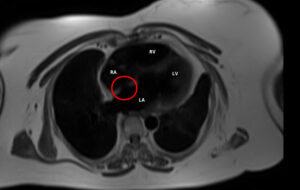

A 47-year old female presented for evaluation of dyspnea on exertion and hypoxemia observed during a dental procedure. Past medical history included closure of patent ductus arteriosus at 11 months and closure of a ventricular septal defect at 15 months. On exam she had a loud P2 and a soft systolic murmur at tricuspid area. Resting O2 saturations were 95%, on exercise O2 saturation dropped to 79%. CT chest showed ground glass opacities, enlarged pulmonary arteries (PAs) and no acute pulmonary embolism. She had a negative nuclear stress test, pulmonary function testing with mild restriction, an echo with a right ventricular systolic pressure of 40mmHg and a small secundum atrial septal defect (ASD). Cardiac MRI showed mildly decreased right ventricular systolic function (RVEF 35%) and a QpQs of 1.1